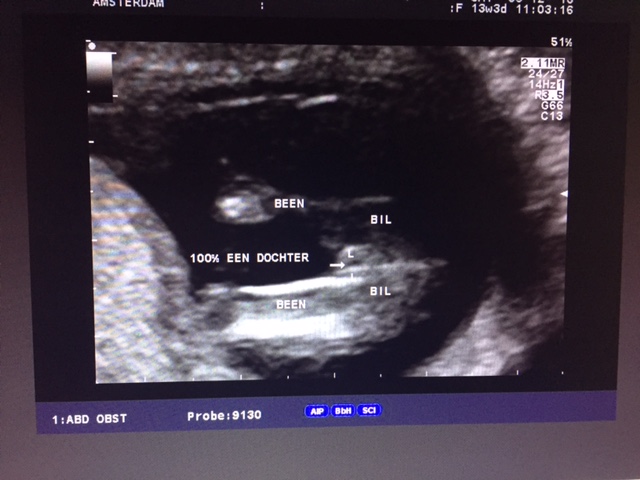

We already had a bloodtest done in Barcelona, but now that I could see it "live" that we are really expecting a daughter I'm believing it !!

So happy!

The text is in Dutch, but it says "100 % girl" ;)

Attachment 28839